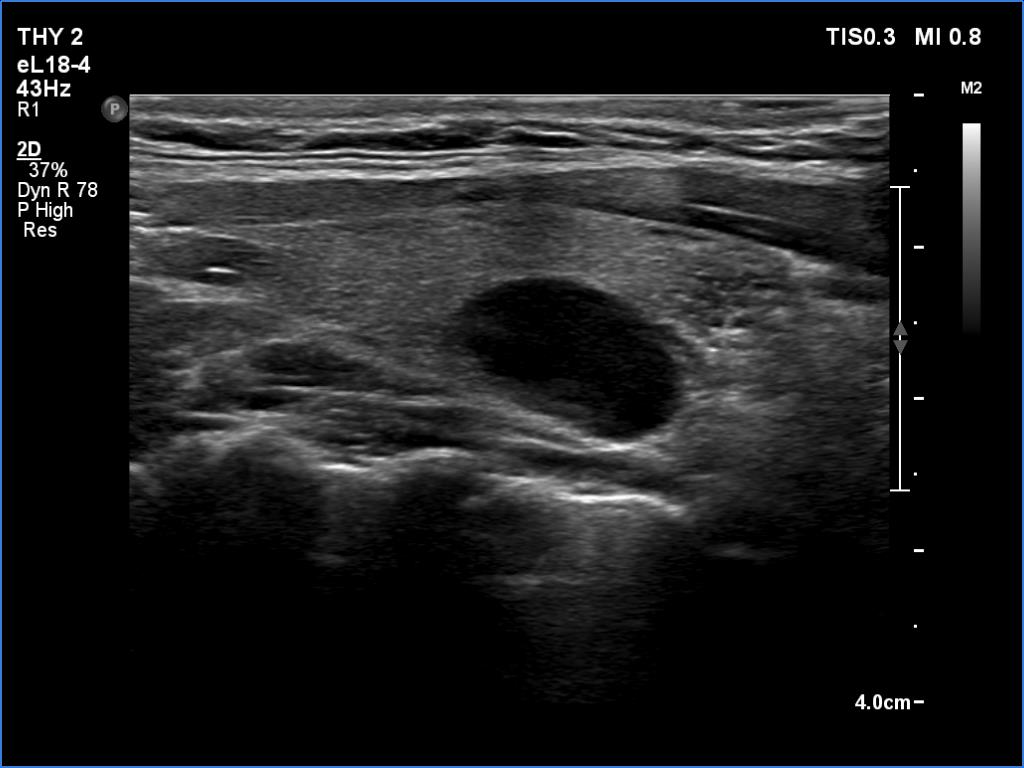

Transverse scan |

Longitudinal scan |

According to the EU-TIRADS, this lesion cannot be regarded as a purely cystic nodule due to the presence of wall-thickening (yellow arrows). The EU-TIRADS defines this lesion as an EU-TIRADS 3 nodule.